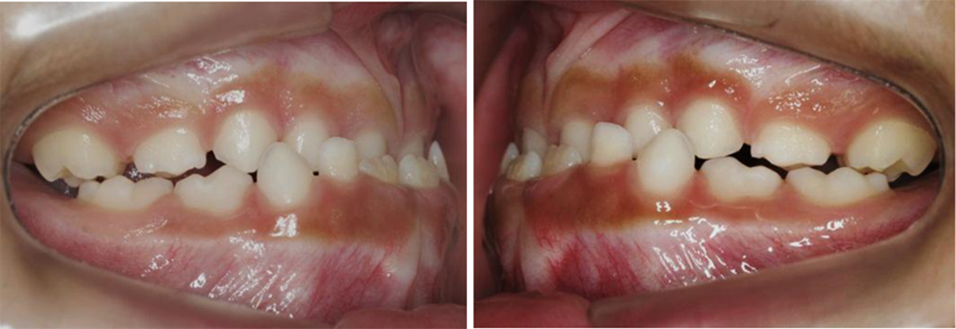

Figura 3. Fotos intrabucales. Vista lateral.

Autor: María Gabriela Flores Bracho. Fuente: Historia Clínica de M. C. M. H. 6 años. 04-2010.